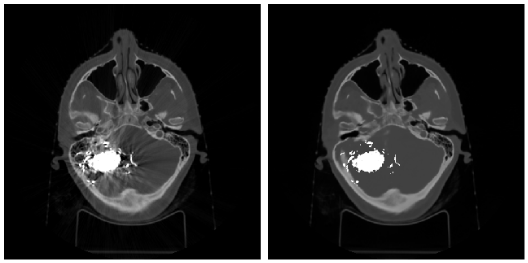

Refer to caption

Figure 4: Examples of processing real corrupted CT scan with intensities in brain window (40+-80 HU). From left to right: original image, Li-MAR output, the output of the proposed solution. Each row corresponds to a different patient.

As we mentioned above, the classical benchmark for metal artifacts refuction methods is Li-MAR. Figure 4 shows examples of our algorithm and Li-MAR work on real CT scans of the patients with high-density objects that cause artifacts on the images. It is visible in the brain window that the model restores distinguishable brain structures well. Also, it is important to mention that the qualitative expert analysis using CT studies of patients with AVMs demonstrates that the method achieves impressive results on scans with large metal regions, which caused significant image distortion. An example is shown in Figure 5.

Figure 5: An example of a CT scan with large metal-containing object causing significant distortion (left) and the output of the proposed solution (right).